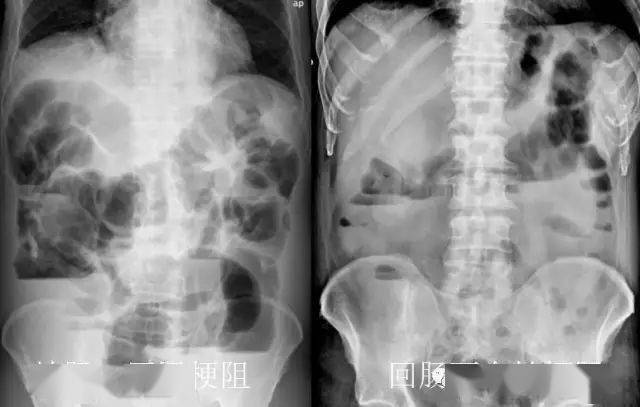

肠梗阻腹部平片

肠梗阻腹部平片,肠梗阻的症状初期

梗阻段以上空肠,回肠内可见多发长短不一,阶梯样气液平面,管腔扩张

梗阻发生后的4~6小时,腹平片上即可见胀气的肠袢及多数气液平面.

1,x线卧位腹部平片:充气扩大的小肠呈连贯的透亮影,横贯腹腔之大部